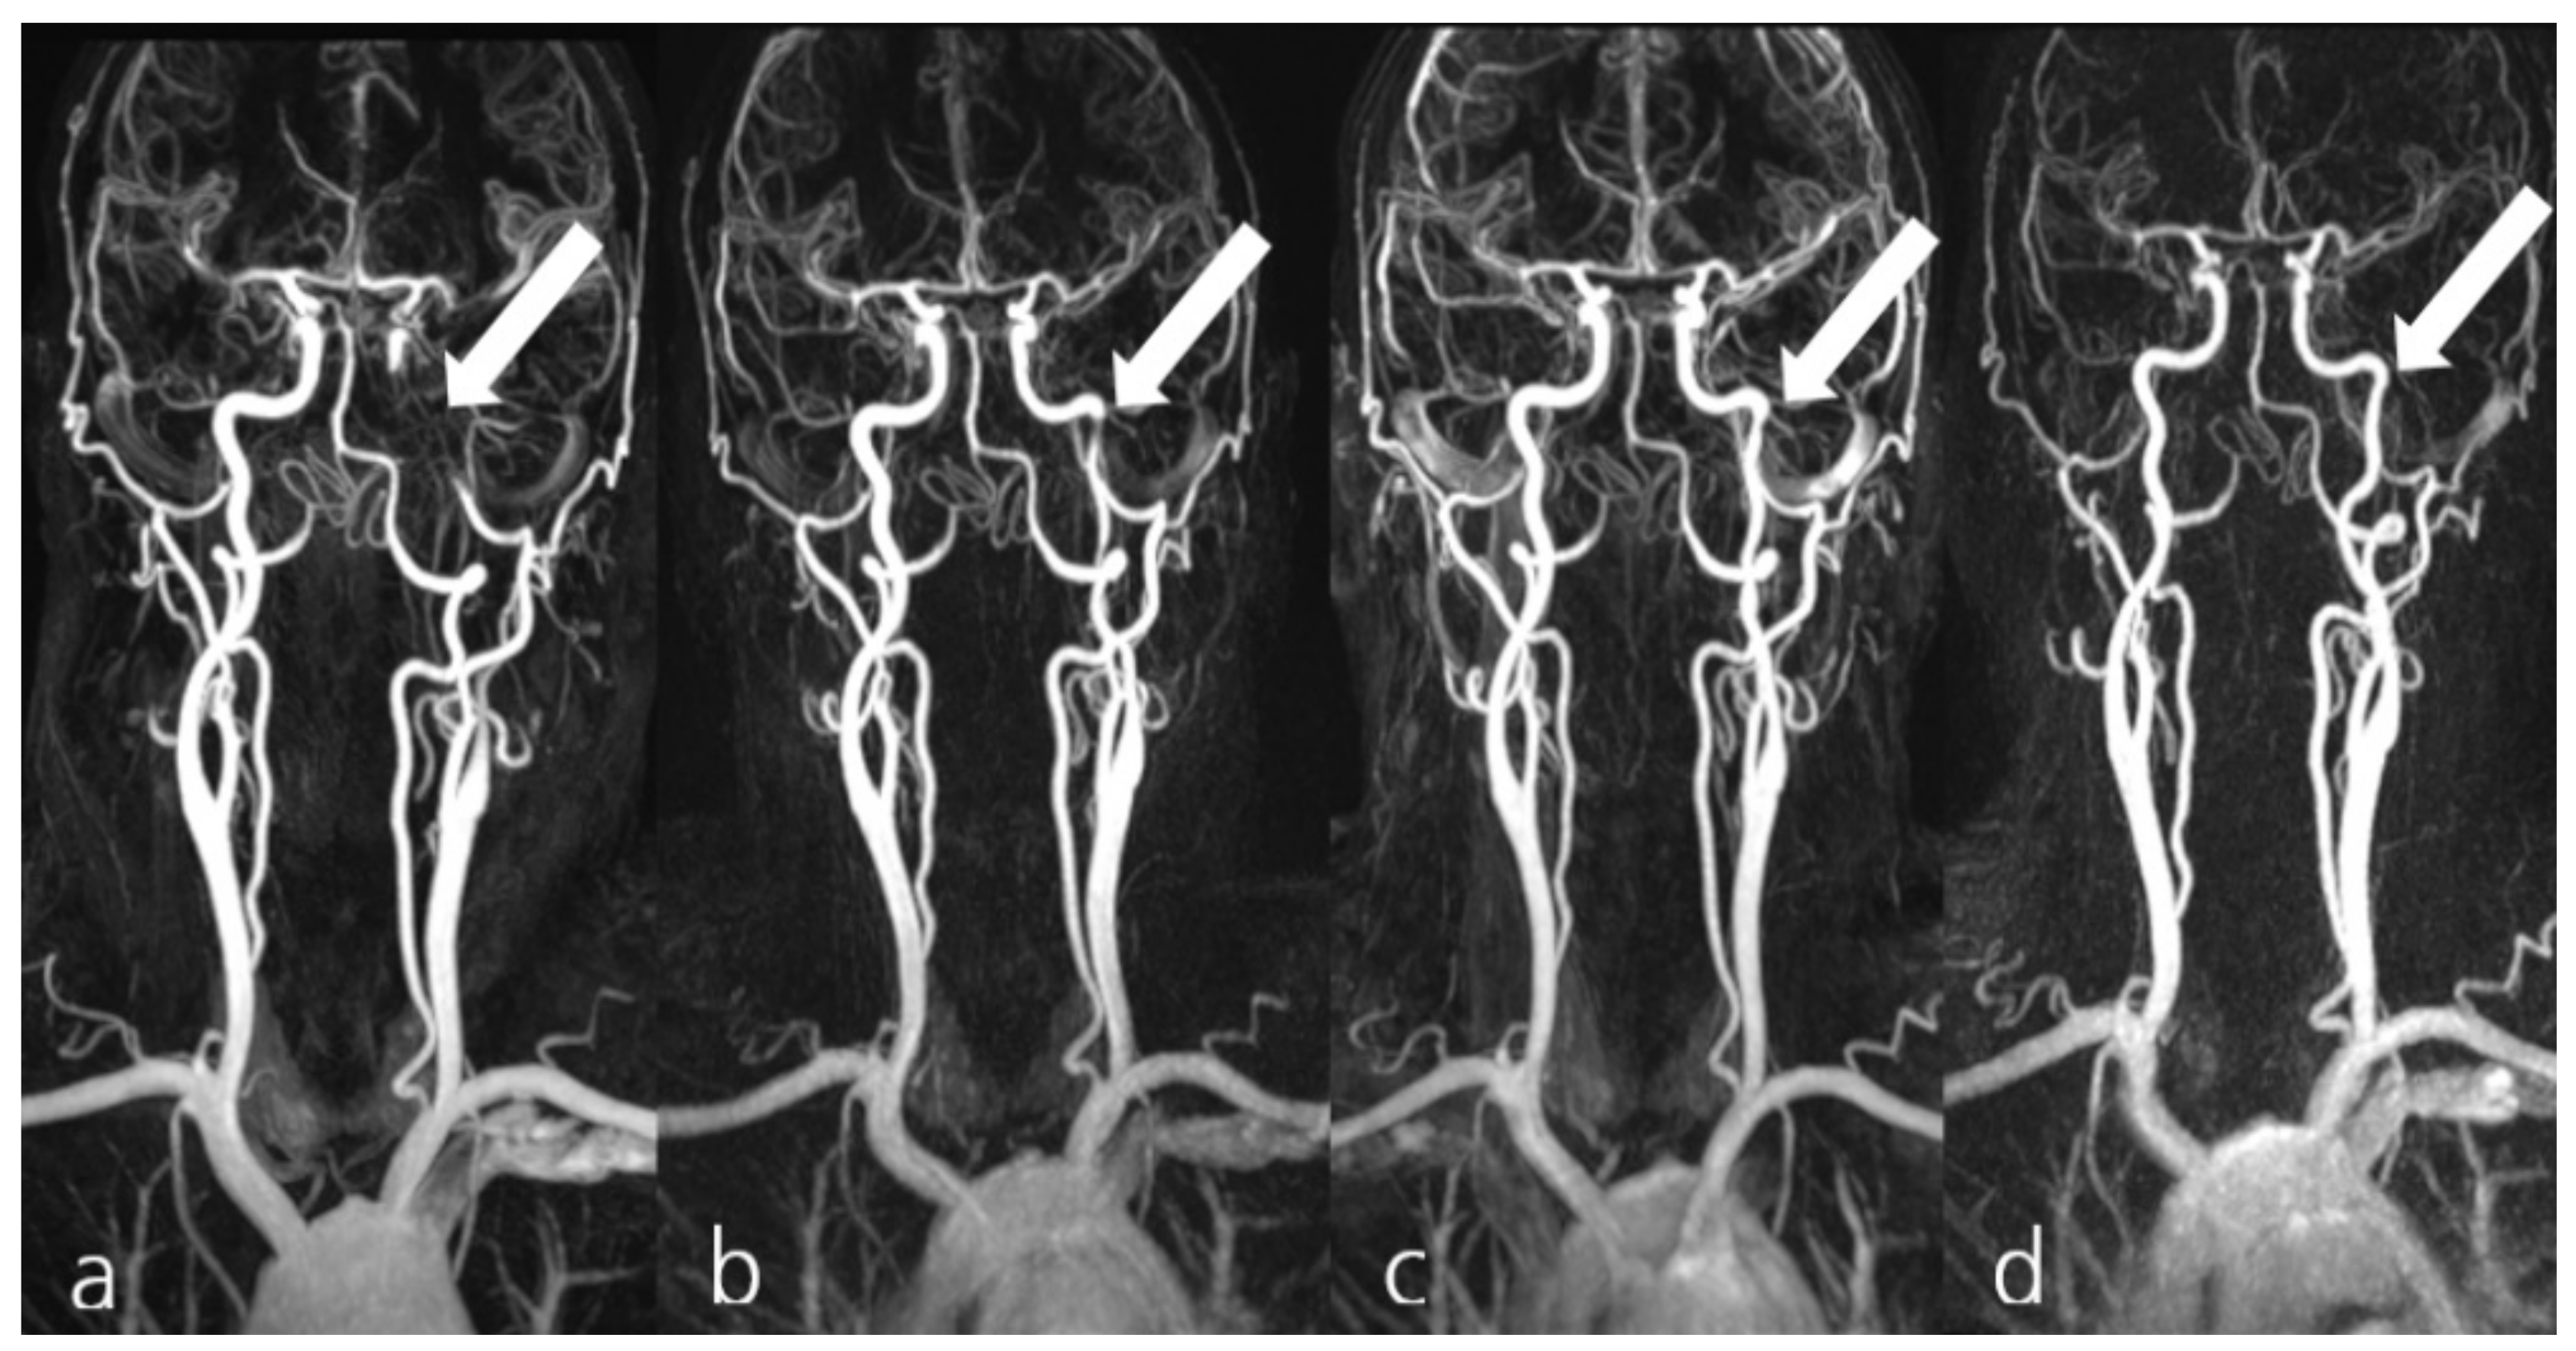

Figure 3. Exemplary display of patient #1 from group II, presenting with a spontaneous dissection of the left internal carotid artery (a, arrow). MRA confirmed the collateral supply for the occluded artery from the right-hand anterior circulation (a). The patient received 2× 150 mg dabigatran, 1× 100 mg ASA and 2× 90 mg ticagrelor PO daily. Follow-up MRA examinations 16 days (b), 29 days (c), and 141 days (d) demonstrated the progressive recanalization of the dissected artery (arrows).